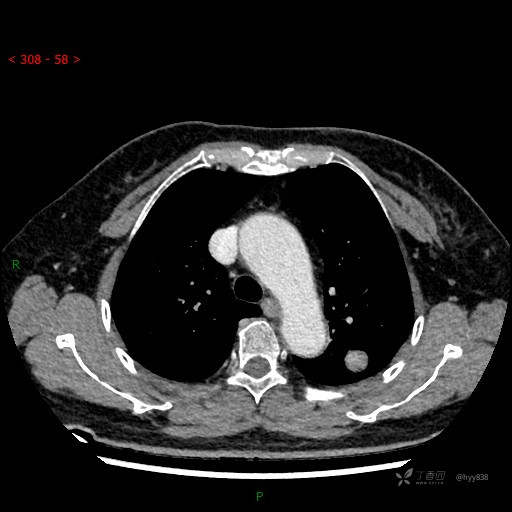

胸部CT平扫